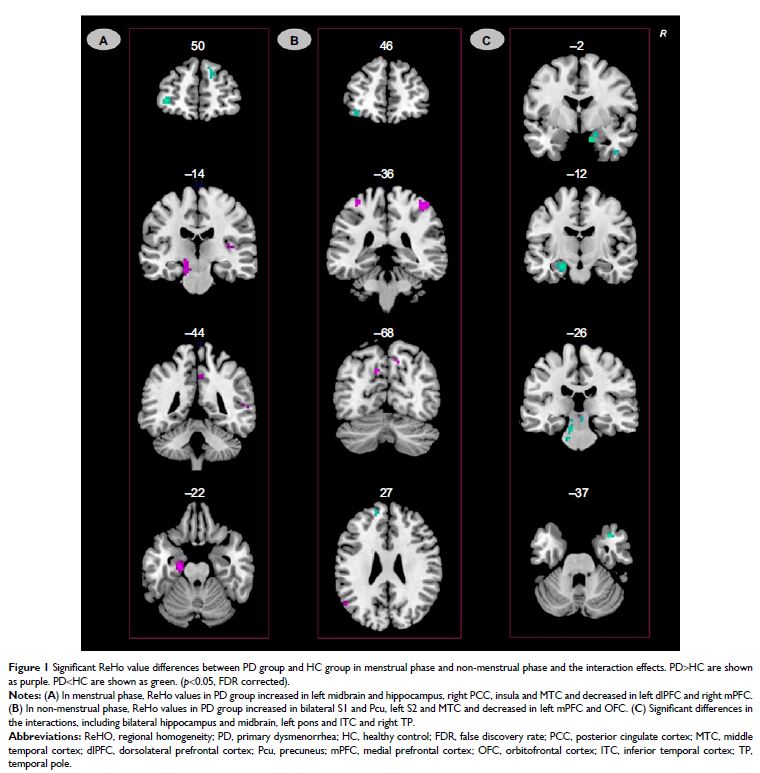

- 作者:Lingmin Jin, Xuejuan Yang, Peng Liu, Jinbo Sun, Fei Chen, Ziliang Xu, Wei Qin, Jie Tian

- 期刊:Journal of Pain Research